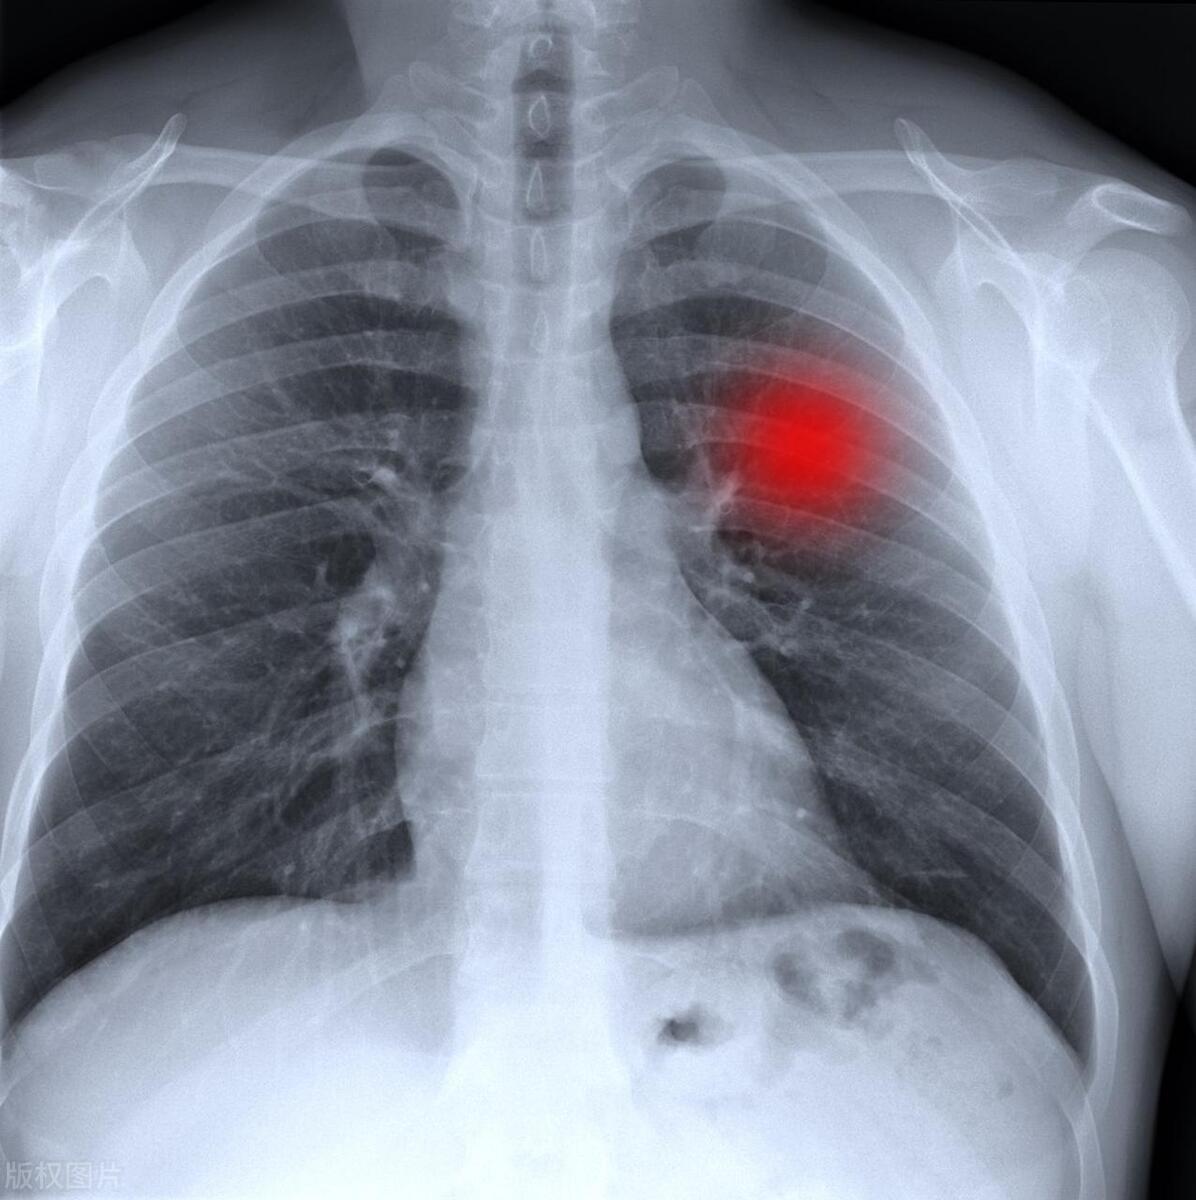

早期诊断是提高肺癌患者生存率的关键。在早期阶段发现肺癌时,治疗通常更容易,生存率更高。定期体检、肺部CT扫描和筛查可以帮助早期诊断。

如果肺癌在早期阶段被诊断出来,并且可以进行手术切除或其他治疗,生存率会显著提高。一些肺癌可能在早期阶段没有明显的症状,因此定期体检和筛查非常重要。

影像学检查: 定期进行影像学检查,如CT扫描、X光和MRI,有助于监测肿瘤的生长和变化。这些检查可以提供有关肺癌是否有进展的信息。